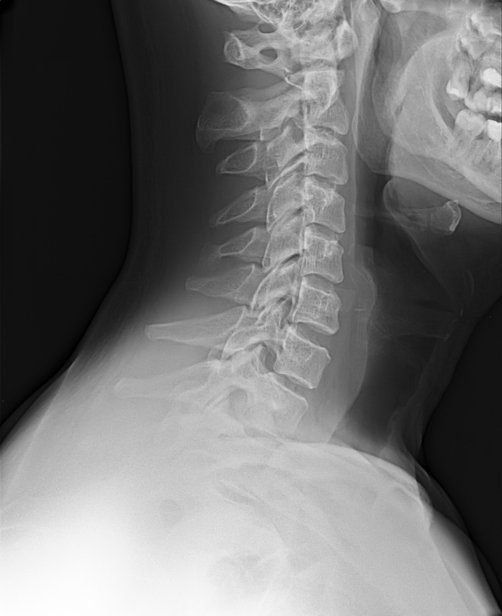

Для визуализации костных изменений назначается рентгенография области соединения позвоночника и черепа. Информативным методом служит также КТ соответствующей зоны.